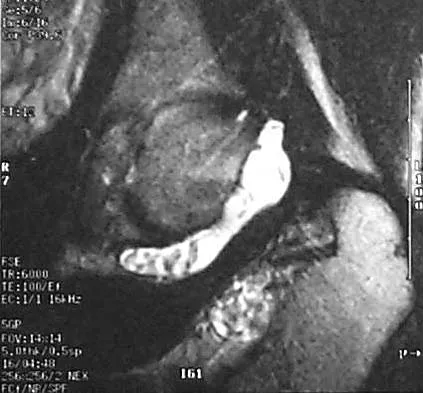

Figure 42 shows the sagittal T2-weighted MRI scan of a patient's right knee. These findings are most commonly seen with a complete tear of the

Explanation

The MRI scan reveals disruption of the lateral capsule and ligaments with fluid in the soft tissues laterally. Additionally, there is a large bone bruise on the medial femoral condyle. This combination indicates injury to the posterolateral complex. These injuries often have coexisting anterior and/or posterior cruciate ligament injuries. Failure to recognize the posterolateral corner injury can lead to failure of anterior or posterior cruciate ligament reconstructions. LaPrade RF, Gilbert TJ, Bollom TS, et al: The magnetic resonance imaging appearance of individual structures of the posterolateral knee: A prospective study of normal knees and knees with surgically verified grade III injuries. Am J Sports Med 2000;28:191-199.